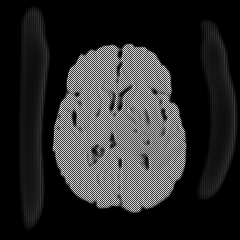

Main Module . The main module aims to generate two selective cuts, which separate the normal and abnormal information in an input image. The follows an encoder-decoder architecture like the U-Net, including one encoder and two decoders. The encoder extracts features of an input image , which could be an image located within or outside of the reference distribution , a collection of normal images. One decoder, the second upsampling branch, is designed to generate a “fence” cut that is constrained by an image fence formed by . The aims to generate an image and tries to fool the discriminator . The other decoder, the first unsampling branch, is designed to generate another “wild” cut , which captures leftover image content that is not included in . As a result, the produces another images to complement the fence-cut output . Since the wile-cut output is complementary to the fence-cut output, image information that can not be covered by the reference distribution would be included in the while-cut output, like the anomaly. The complementary relation between these two cuts and is enforced by a positive Dice loss, i.e., a “disjoincy” loss as discussed in the paragraph of Loss Functions. Figure 2 demonstrates the “disjoincy” of and , like their complementary histogram distribution and different thresholded images at different peaks.

Except for a weak guidance of the “disjoincy” loss for the “wild” cut, we adopt a reconstruction branch to make sure our two selective cuts include enough information to constrcut a coarse version of the original input. The reconstructor consists of a convolution layer with the Sigmoid as the activation function, which is applied on the concatenation of the two-cut outputs and to regenerate the input image back. This reconstructor ensures that the does not generate an image far from the input image and also ensures that the does not generate an empty image if the anomaly or novelty exists. Figure 3 shows the histogram separation of the reconstructed images, compared to the original input images which present complex histogram peaks and have difficulty in separating the brain tumor from backgorund and other tissues via a simple thresholding. The discontinuous histogram distribution of is inherited from the two generated sub-images and through a simple weighted combination. As a result, the segmentation task becomes relatively easy to be done on the reconstructed image .